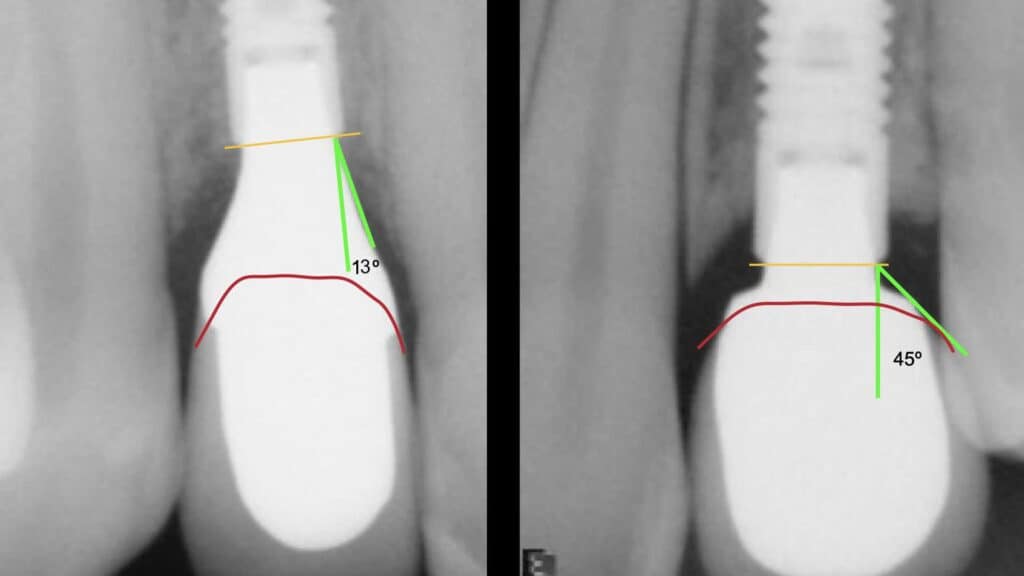

In particular what we call the “Deep” angle, is a critical determinant of the early marginal bone loss or “remodelling”. This is not the approximate “emergence angle” as drawn on the contour of periapical radiographs, but the angle at the bottom of the implant abutment, exactly where it ascends from the bone level. Place an abutment with Deep angle close to 45o and you will end up losing much more marginal bone due to remodelling, than with a narrow 15o abutment (Souza 2018). If the deep angle is so important to maintain marginal bone loss, do the Tissue Level implants have any advantage to that end?

As much as the optimal individual design at the left would be not possible with a Tissue Level implant, also the unfavourable design to the right would have not been allowed on a Tissue Level implant!